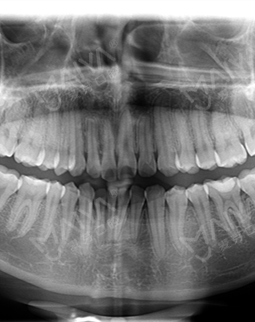

一大半的牙套都被我戴完啦!今天又来复诊取牙套了,现在摘戴牙套已经轻车熟路了,医生说我的咬合也慢慢调整好了,平时出门带个包,一个手机,还有一盒牙线,相比之前我发现我更爱自己的牙齿了,而且懂了很多牙齿的专业术语,什么数字化全景片啊、牙齿咬合啊、、、现学现卖,哈哈哈哈.....复诊完又逛街花money了,图片来自于偷拍我的闺蜜,她说我整个人都不一样了,真的觉得小牙套改变不是整口牙,而是整个人~~~想矫正的仙女抓紧时间,上次我复诊的时候,刚好碰上有活动,我另一个朋友省了很多钱,可以去看一下

身边的闺蜜都是工作后开始矫牙的,爱美的我又被那种透明的牙套种草了~~跟着闺蜜一起来矫正,其实我真的是没有想到这里的服务和环境真的一点都不差,而且从挂号到医生看诊,都有人服务,虽然当天人多了点,但是体验还是不错的! 然后呢,拍个片,医生给定方案,取了模,说过几天就有定制的牙套啦,想想还挺开心的....